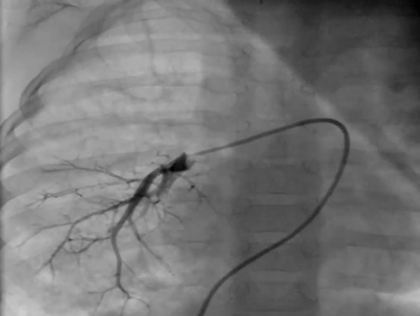

Despite the improvement of PH, he suffered from focal right lower lobe pneumonia complicated with pulmonary hemorrhage repeatedly from the age of 2 years and 4 months. At 3 years and 5 months of age, we performed further examinations including cardiac catheterization. On chest X-ray, there was diffuse pulmonary congestion in both lung fields without pleural effusion (Fig. 1d). The ejection fraction was 63%, and the ratio of right-to-left ventricular systolic blood pressure was estimated to be 0.52 by echocardiography. The blood flow velocity was 2.1 m/s in the right pulmonary veins indicating the remaining of right PVS. On cardiac catheterization showed the descending aortic pressure and the pulmonary arterial pressure was 70/44 (55) mmHg and 42/17 (29) mmHg, respectively. The pulmonary vascular resistances calculated using pulmonary blood flow ratio (right : left=3 : 97) by lung perfusion scintigraphy were 38.9 units m2 on the right and 3.60 units m2 on the left (Table 1), indicating that the pulmonary vascular resistance was improved by medical intervention. Right pulmonary arteriography revealed diminished pulmonary vascular bed, right lower PV obstruction (Movie).

Movie 1